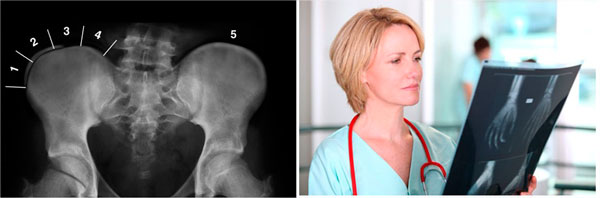

¿Como determinar el potencial de crecimiento óseo?

El mas usado es el signo de risser que nos permite evaluar la aparición del núcleo de osificación en la cresta iliaca

¿Cómo se determina el potencial de crecimiento óseo?

En cada visita al especialista evaluara:

• La talla de la paciente

• Además, en la radiografía puede verse el Signo de Risser, un marcador de madurez ósea visible en la pelvis y que indica cuánto queda para alcanzar la madurez ósea.

• También se tiene en cuenta la presencia de signos propios de la pubertad. En las niñas se utiliza la aparición de periodos menstruales y el desarrollo de la mama, mientras que en los niños pueden valorarse los cambios en la voz y el vello facial.

Estos indicadores de madurez ósea no siempre se correlacionan y puede ser aconsejable realizar una radiografía con objeto de evaluar los núcleos de crecimiento de los huesos de la mano y en la pelvis.